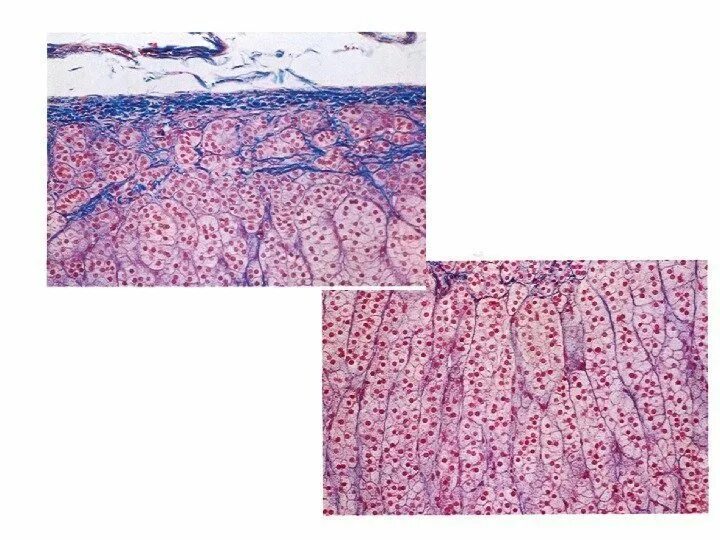

Гистология эндокринных желез